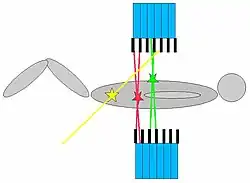

Zufallskoinzidenzen (Randoms)

Randoms gehören zu den unerwünschten Ereignissen. Werden zwei Szintillationen in zwei in Koinzidenz geschalteten Kristallen innerhalb des Koinzidenzzeitfensters detektiert, werden sie als Annihilation interpretiert.

Es ist jedoch möglich, dass zwei Singles registriert werden, die an verschiedenen Orten im Untersuchungsvolumen zufällig zur selben Zeit entstanden sind. Dies wird dann ebenso – in diesem Fall jedoch fälschlicherweise – als Annihilation interpretiert und geht in die Bildrekonstruktion ein.

Die Entstehungswahrscheinlichkeit von Zufallskoinzidenzen (Randoms) lässt sich verringern durch:

- eine niedrige applizierte Nukliddosis,

- ein kleines Koinzidenzzeitfenster,

- eine große Zahl von Detektoren,

- durch Verringerung der Zahl der gemessenen Singles (z. B. durch Verwendung von Septen = 2D Aufnahmemodus)

- durch Nutzung der „Time-of-flight“-Datenakquisitionstechnik

Die Zahl der gemessenen Randoms steigt mit steigender Zahl an Singles stark an.

Gestreute Koinzidenzen (Scatter)

Streustrahlung gehört zu den unerwünschten Ereignissen. Wird ein Photon auf dem Weg zum Detektor gestreut, so ändert es seine Richtung. Da der Ortsbestimmung im PET jedoch immer eine gerade Strecke zwischen zwei zeitgleich aufgetretenen Ereignissen zugrunde liegt, führt dies zu einer Fehllokalisation. Durch die Streuung verliert ein Photon jedoch an Energie. Streustrahlung kann somit ausgeblendet werden, indem eine Szintillation nur dann gezählt wird, wenn sie im Detektor eine bestimmte Energieschwelle überschreitet. Die Verwendung einer unteren Energieschwelle ist daher eine wirkungsvolle Methode zur Unterdrückung gestreuter Koinzidenzen. Allerdings wird dieser Ansatz durch die endliche Energieauflösung des Detektors begrenzt.